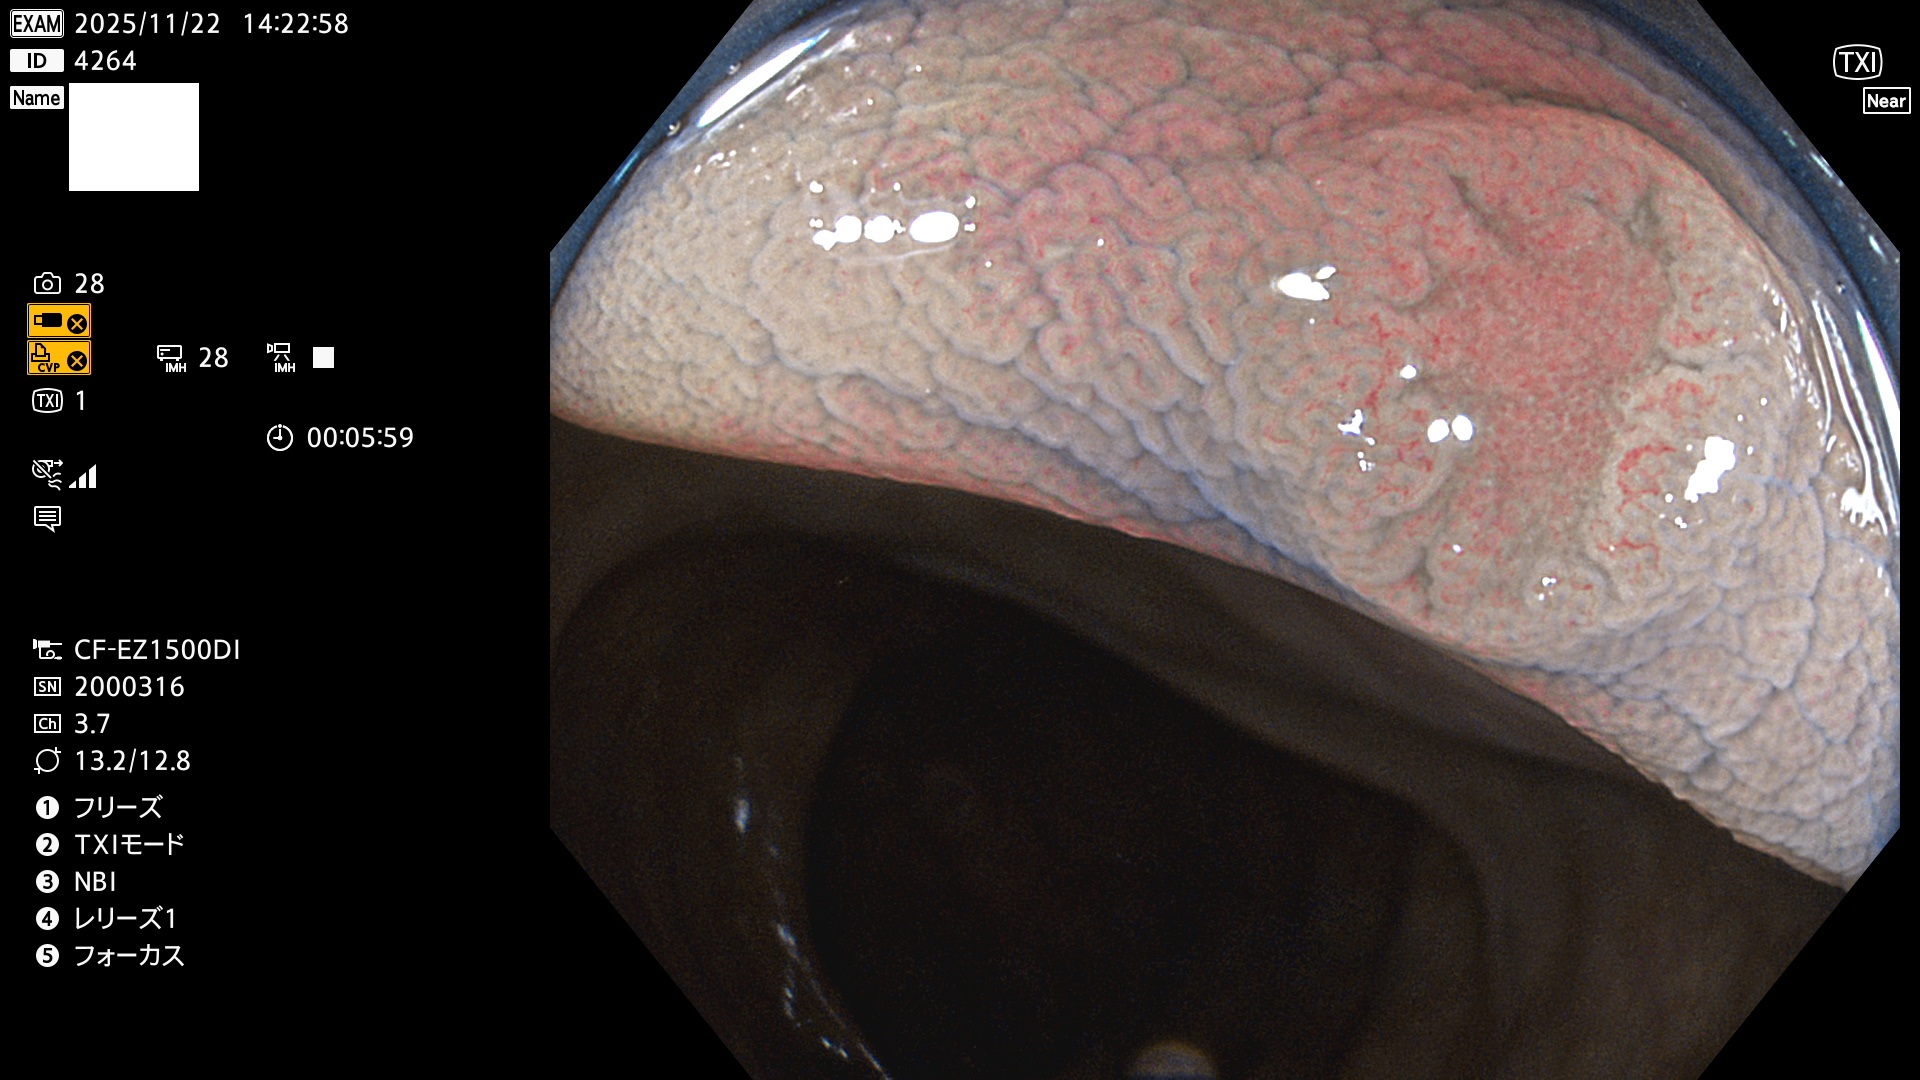

完全に平坦な物をUb、陥凹している物をUcと呼びます。Ubは認識が困難で、Ucはびらん(炎症)と紛らわしいために見落とされやすく、「内視鏡後・大腸癌」の原因になります。

専門的)Uc=De Novo癌? 内視鏡の解像度が低かった時代、このような説もありました。しかし今日の高精度内視鏡では良性の微小なUc型腺腫(APC遺伝子異常の腺腫)が日常的に見つかります。Ucこそが多段階発癌(Adenoma-Carcinoma Sequence)のMain Routeです。

毎週の検査(木・金・土・日)に発見されたUbとUc型・腺腫を、その週の日曜の夜にUPし1週間、提示します。

2025年11月20日〜11月23日の4日間(40件)8個 (Uc_ADR=8個/40人=20%)